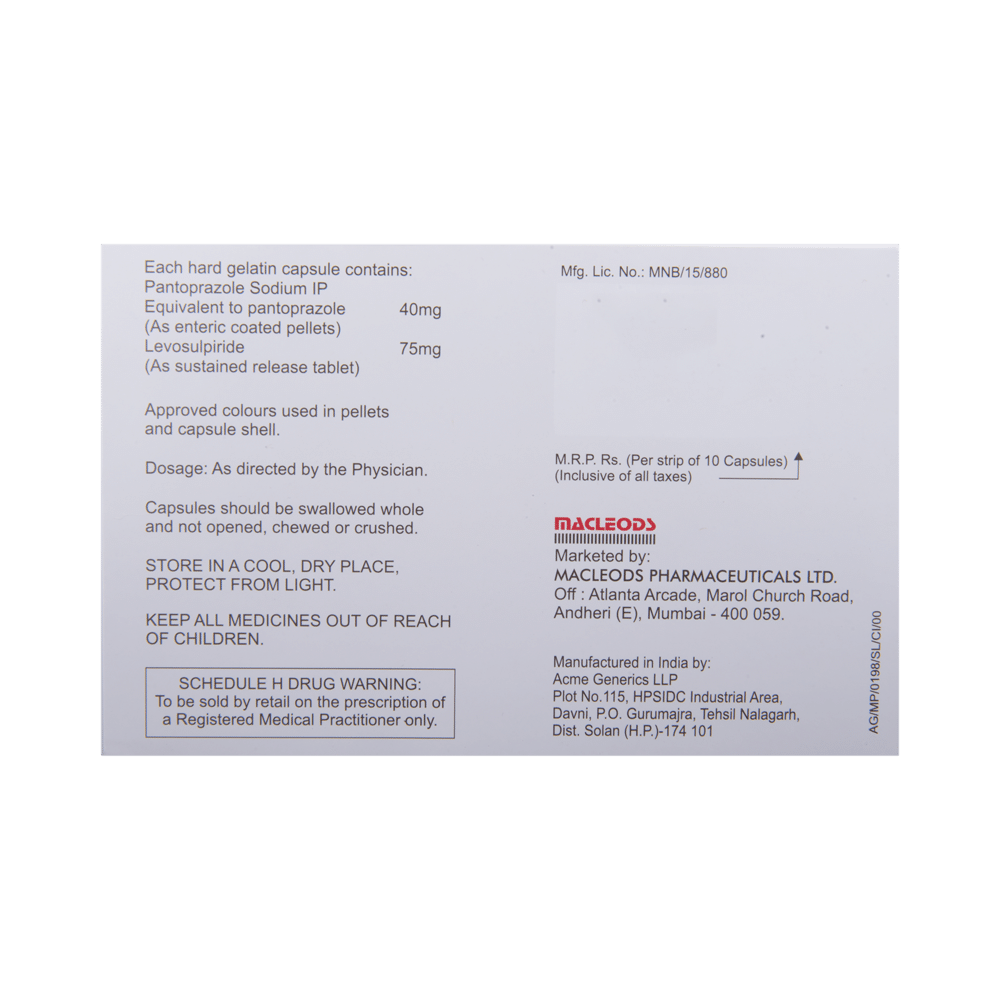

| Salt Composition: | Levosulpiride (75mg) + Pantoprazole (40mg) |

| Manufacturer: | Macleods Pharmaceuticals Pvt Ltd |

| Storage: | Below 25 degree celcius |

Take this medicine in the dose and duration as advised by your doctor. Swallow it as a whole. Do not chew, crush or break it. Nupenta LS Capsule SR is to be taken empty stomach.